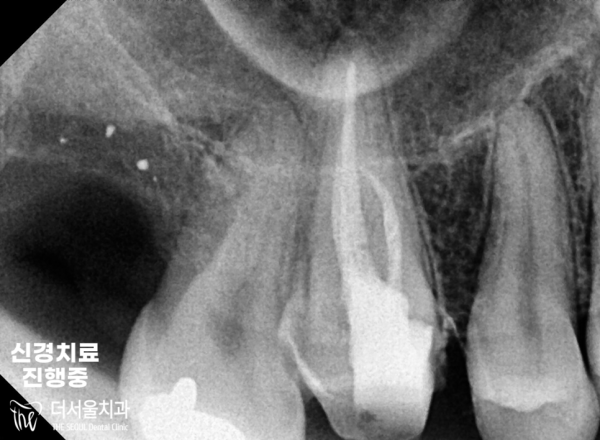

아말감 아래에 있는 2차충치는 아말감을 제거하고 신경치료를 하기로하였습니다.

꼼꼼하게 감염된 부위를 제거하고 충전재료를 넣은뒤에 지르코니아 크라운으로 치료를

마무리하게되었습니다.

The secondary cavity under the amalgam decided to remove the amalgam and perform neurotreatment.

Carefully remove the infected area, add filling material, and treat it with zirconia crown

We're going to wrap this up.